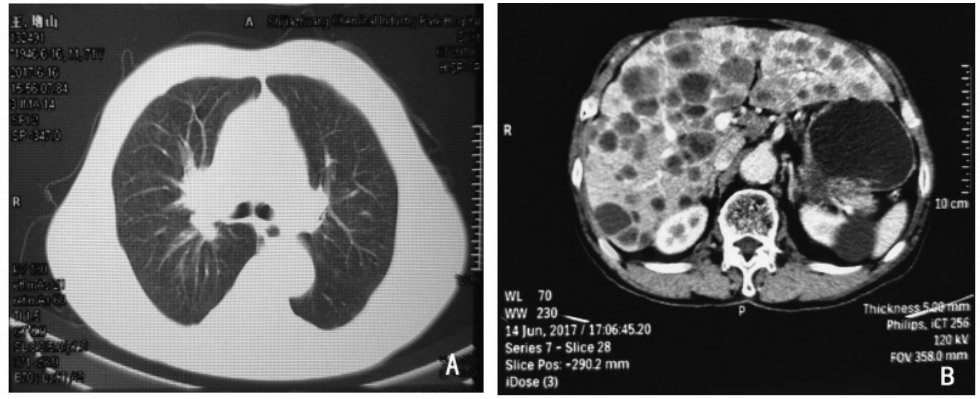

周围型小细胞肺癌ct

周围型小细胞肺癌ct,小细胞肺癌ct

小细胞肺癌一例

小细胞肺癌ct

小细胞肺癌